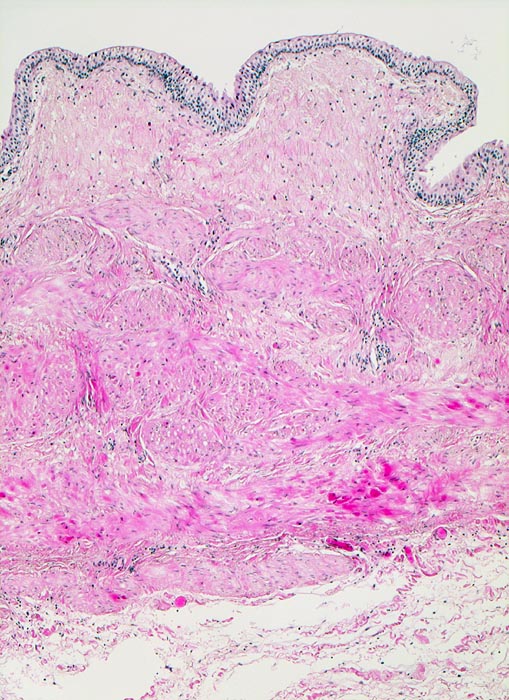

• In der Mitte oben ist ein Harnblasenfragment mit tumorfreien Anteilen der Harnblasenwandmuskulatur erkennbar. Dieses Fragment ist bedeckt von einem aus wenigen Zellagen bestehenden dyskohäsiven Urothel, von dem sich einzelne Zellen ablösen. Die Zellkerne sind pleomorph, hyperchromatisch und vergrössert(Carcinoma in situ des tumorfernen Urothels).

• Invasion der Lamina propria (Tumorfragmente links): Kleine Tumorzellgruppen oder Einzelzellen haben die Basalmembran an wenigen Stellen durchbrochen und liegen in der Lamina propria.

• Begleitendes dichtes gemischtes Entzündungsinfiltrat.